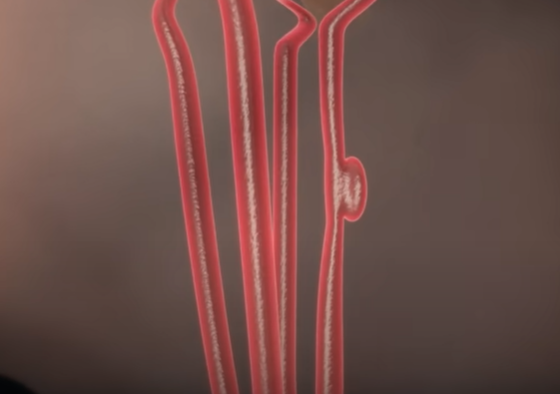

뇌동맥류

약해진 혈관 벽이 늘어나 마치 꽈리 모양으로 부풀어 오른 뇌동맥류는 터지는 순간 극심한 두통을 유발한다.

가장 위험한 게 뇌동맥류 파열에 의한 지주막하 출혈이다. 처음 출혈이 생기고 두통이 어느 정도 해소된 다음에는 환자가 마치 병이 나은 것처럼 생각하는데 만약 뇌동맥류가 터진 상태로 출혈이 멈추지 않으면 급사를 하게 된다.

뇌에 있는 동맥은 지주막하 공간이라는 뇌척수액이 가득 차 있는 곳에 있어서 마치 물에 동맥이 떠 있는 형태이다. 그곳에 있는 동맥류에 꽈리가 생겨서 파열되면 뇌 전체로 피가 퍼지기에 순식간에 뇌압을 상승시킨다. 뇌동맥류가 터지는 정도에 따라서 임상적으로 등급을 나누는데 한두 시간 정도 참을 수 있을 정도의 가벼운 두통부터 급사하는 정도까지, 출혈량이나 파열 정도에 따라 다양한 임상 증상이 생긴다.

뇌동맥류 증상, 형태

아래 사진의 특정 환자의 경우, 모두 6개의 뇌동맥류가 자리 잡고 있었다. 뇌동맥류는 터지기 전에는 별다른 증상이 없지만 크기가 클 경우 두통을 일으키기도 한다.

뇌동맥류의 크기가 가장 중요하다. 과거에는 10mm 이상의 뇌동맥류를 큰 동맥류라 했는데, 지금은 가장 긴 직경이 7mm 이상 되는 크기면 위험하다고 한다. 또한, 모양도 중요한데 밋밋하고 평평하게 생긴 뇌동맥류는 파열 위험성이 적으나, 매끈한 표면이 아닌 불룩한 형태의 울퉁불퉁한 형태나 뾰족한 뇌동맥류는 위험할 수 있다. 혈압이 높거나, 흠 연하는 경우, 여성이나 고령의 환자는 뇌동맥류가 커질 확률이 크다.

뇌동맥류 치료 : 클립 결찰술, 코일 색전술

직접 머리를 열어 뇌동맥류를 클립으로 묶어주는 경부 결찰술과

혈관을 따라 와이어를 삽입한 뇌동맥류 안쪽 공간을 가느다란 코일로 채워주는 코일 색전술이 있다.

둘 다 뇌동맥류로 가는 혈류를 차단해 파열을 막아주는 효과가 있다.

대개 개두술, 경부 결찰술을 하는 뇌수술을 받으면 굉장히 위험하고 혈관 내 수술, 즉 코일 색전술은 안전하다 생각하는데 치료법의 결정은 동맥류의 모양에 큰 영향을 받는다. 경부(동맥류가 시작하는 목 부분)가 굉장히 좁고 동맥류 자체가 크면 코일 색전술을 하기 쉽다. 반대로 경부는 넓고 동맥류의 높이는 높지 않은데 위험한 위치에 있을 경우, 코일 색전술을 하면 동맥류가 불거진 부분에 코일일 지지할 곳이 없다. 이 경우 개두술을 하고 경부 결찰술을 시행하는 것이 훨씬 안전하고 효과적이다.